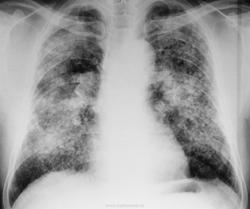

Антракоз. К карбокониозам в настоящее время относят пневмокониозы, вызванные вдыханием углеродсодержащей пыли. Наиболее распространенным видом пневмокониоза этой группы является антракоз, развитие которого обусловлено воздействием пыли каменного угля (антрацит, бурый уголь) или мягкого коксующегося угля.

Пылевую обстановку на современной шахте определяет механизированный выемочный участок, где основными источниками пылеобразования и пылевыделения являются такие технологические процессы, как разрушение угля и породы, погрузка, зачистка угля, передвижка секций крепи и забойного конвейера, транспортировка угля и породы от забоя до поверхности. Пыль угольных шахт смешанная, в ней практически всегда имеется примесь пород, содержащих свободную двуокись кремния, часто в качестве сопутствующей породы присутствуют песчаники и глинистые сланцы, содержащие от 4 до 70% свободной двуокиси кремния. Следовательно, пневмокониоз шахтеров-угольщиков обусловлен воздействием угольной и породной кварцсодержащей пыли и по своей этиологической природе является антракосиликозом. На развитие патологического процесса в легких оказывают также влияние присутствующие в забоях раздражающие газы (при проведении взрывных работ, при использовании дизельной техники) и неблагоприятные микроклиматические условия (сквозняки, обводненность). Антракоз — это пневмокониоз, возникающий при воздействии на легочную ткань угольной пыли.

При рентгенологическом исследовании различают три формы П.: интерстициальную, узелковую и узловую (или конгломеративную), в развитии которых наблюдается определенная стадийность. Узелковые формы П. встречаются чаще всего при силикозе, антракозе и антракосиликозе, при некоторых металлокониозах (сидерозе, баритозе, манганокониозе, бериллиозе, сидеросиликозе). При П., вызываемых вдыханием пыли, не содержащей свободной двуокиси кремния, преобладают интерстициальные формы.